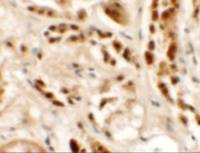

Wild-type (WT) and TET2 knockout (KO) HeLa cell extracts (30 μg) were separated by 5% SDS-PAGE, and the membrane was blotted with TET2 antibody (GTX124227) diluted at 1:500. The HRP-conjugated anti-rabbit IgG antibody (GTX213110-01) was used to detect the primary antibody, and the signal was developed with Trident ECL plus-Enhanced.

Various whole cell extracts (30 μg) were separated by 5% SDS-PAGE, and the membrane was blotted with TET2 antibody (GTX124227) diluted at 1:500.